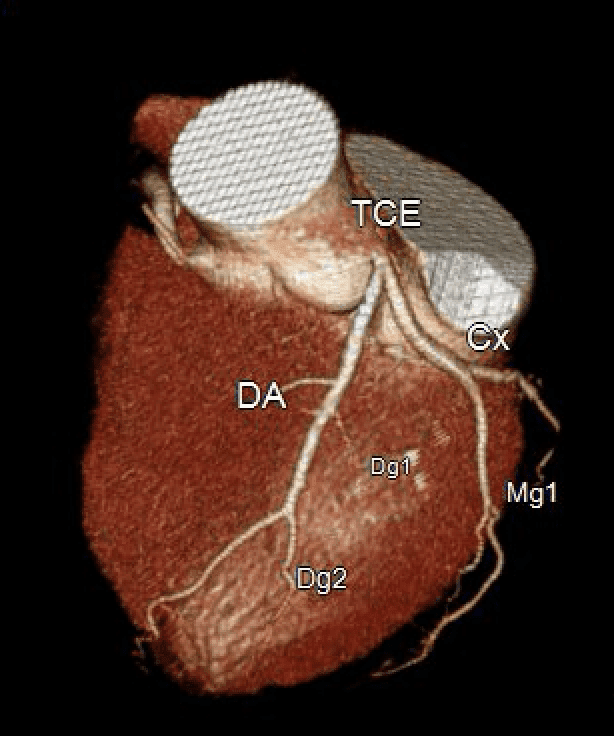

Ja vimos a importância teórica do reconhecimento das características das placa ateroscleróticas pela angiotomografia coronariana, uma vez que esse é o único método não invasivo que pode fornecer essa …

15 MARÇO 2019